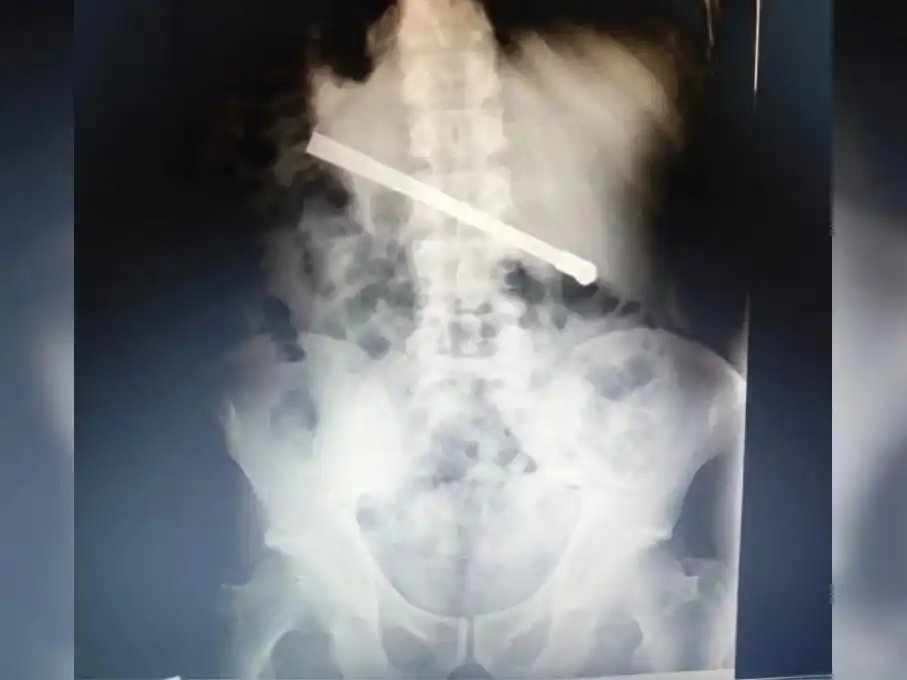

La noche del domingo, un interno del Pabellón de Aislamiento sufrió fuertes dolores después de ingerir una bombilla metálica y fue derivado a un hospital para estudios.

El preso, identificado como R.O.F., alojado en la celda N° 06, fue asistido de inmediato por personal penitenciario. Según trascendió, el hombre había ingerido una bombilla metálica, lo que le provocó un severo malestar abdominal.

El jefe de vigilancia de turno dispuso el traslado del recluso hasta el servicio médico de la unidad. Allí, los profesionales lo revisaron y determinaron que debía ser derivado a un hospital para una mejor atención y estudios más exhaustivos.

El procedimiento se realizó bajo estrictas medidas de seguridad, con cobertura de agentes de Seguridad Externa. Tras la evaluación inicial, se programó su derivación al nosocomio para la mañana siguiente.